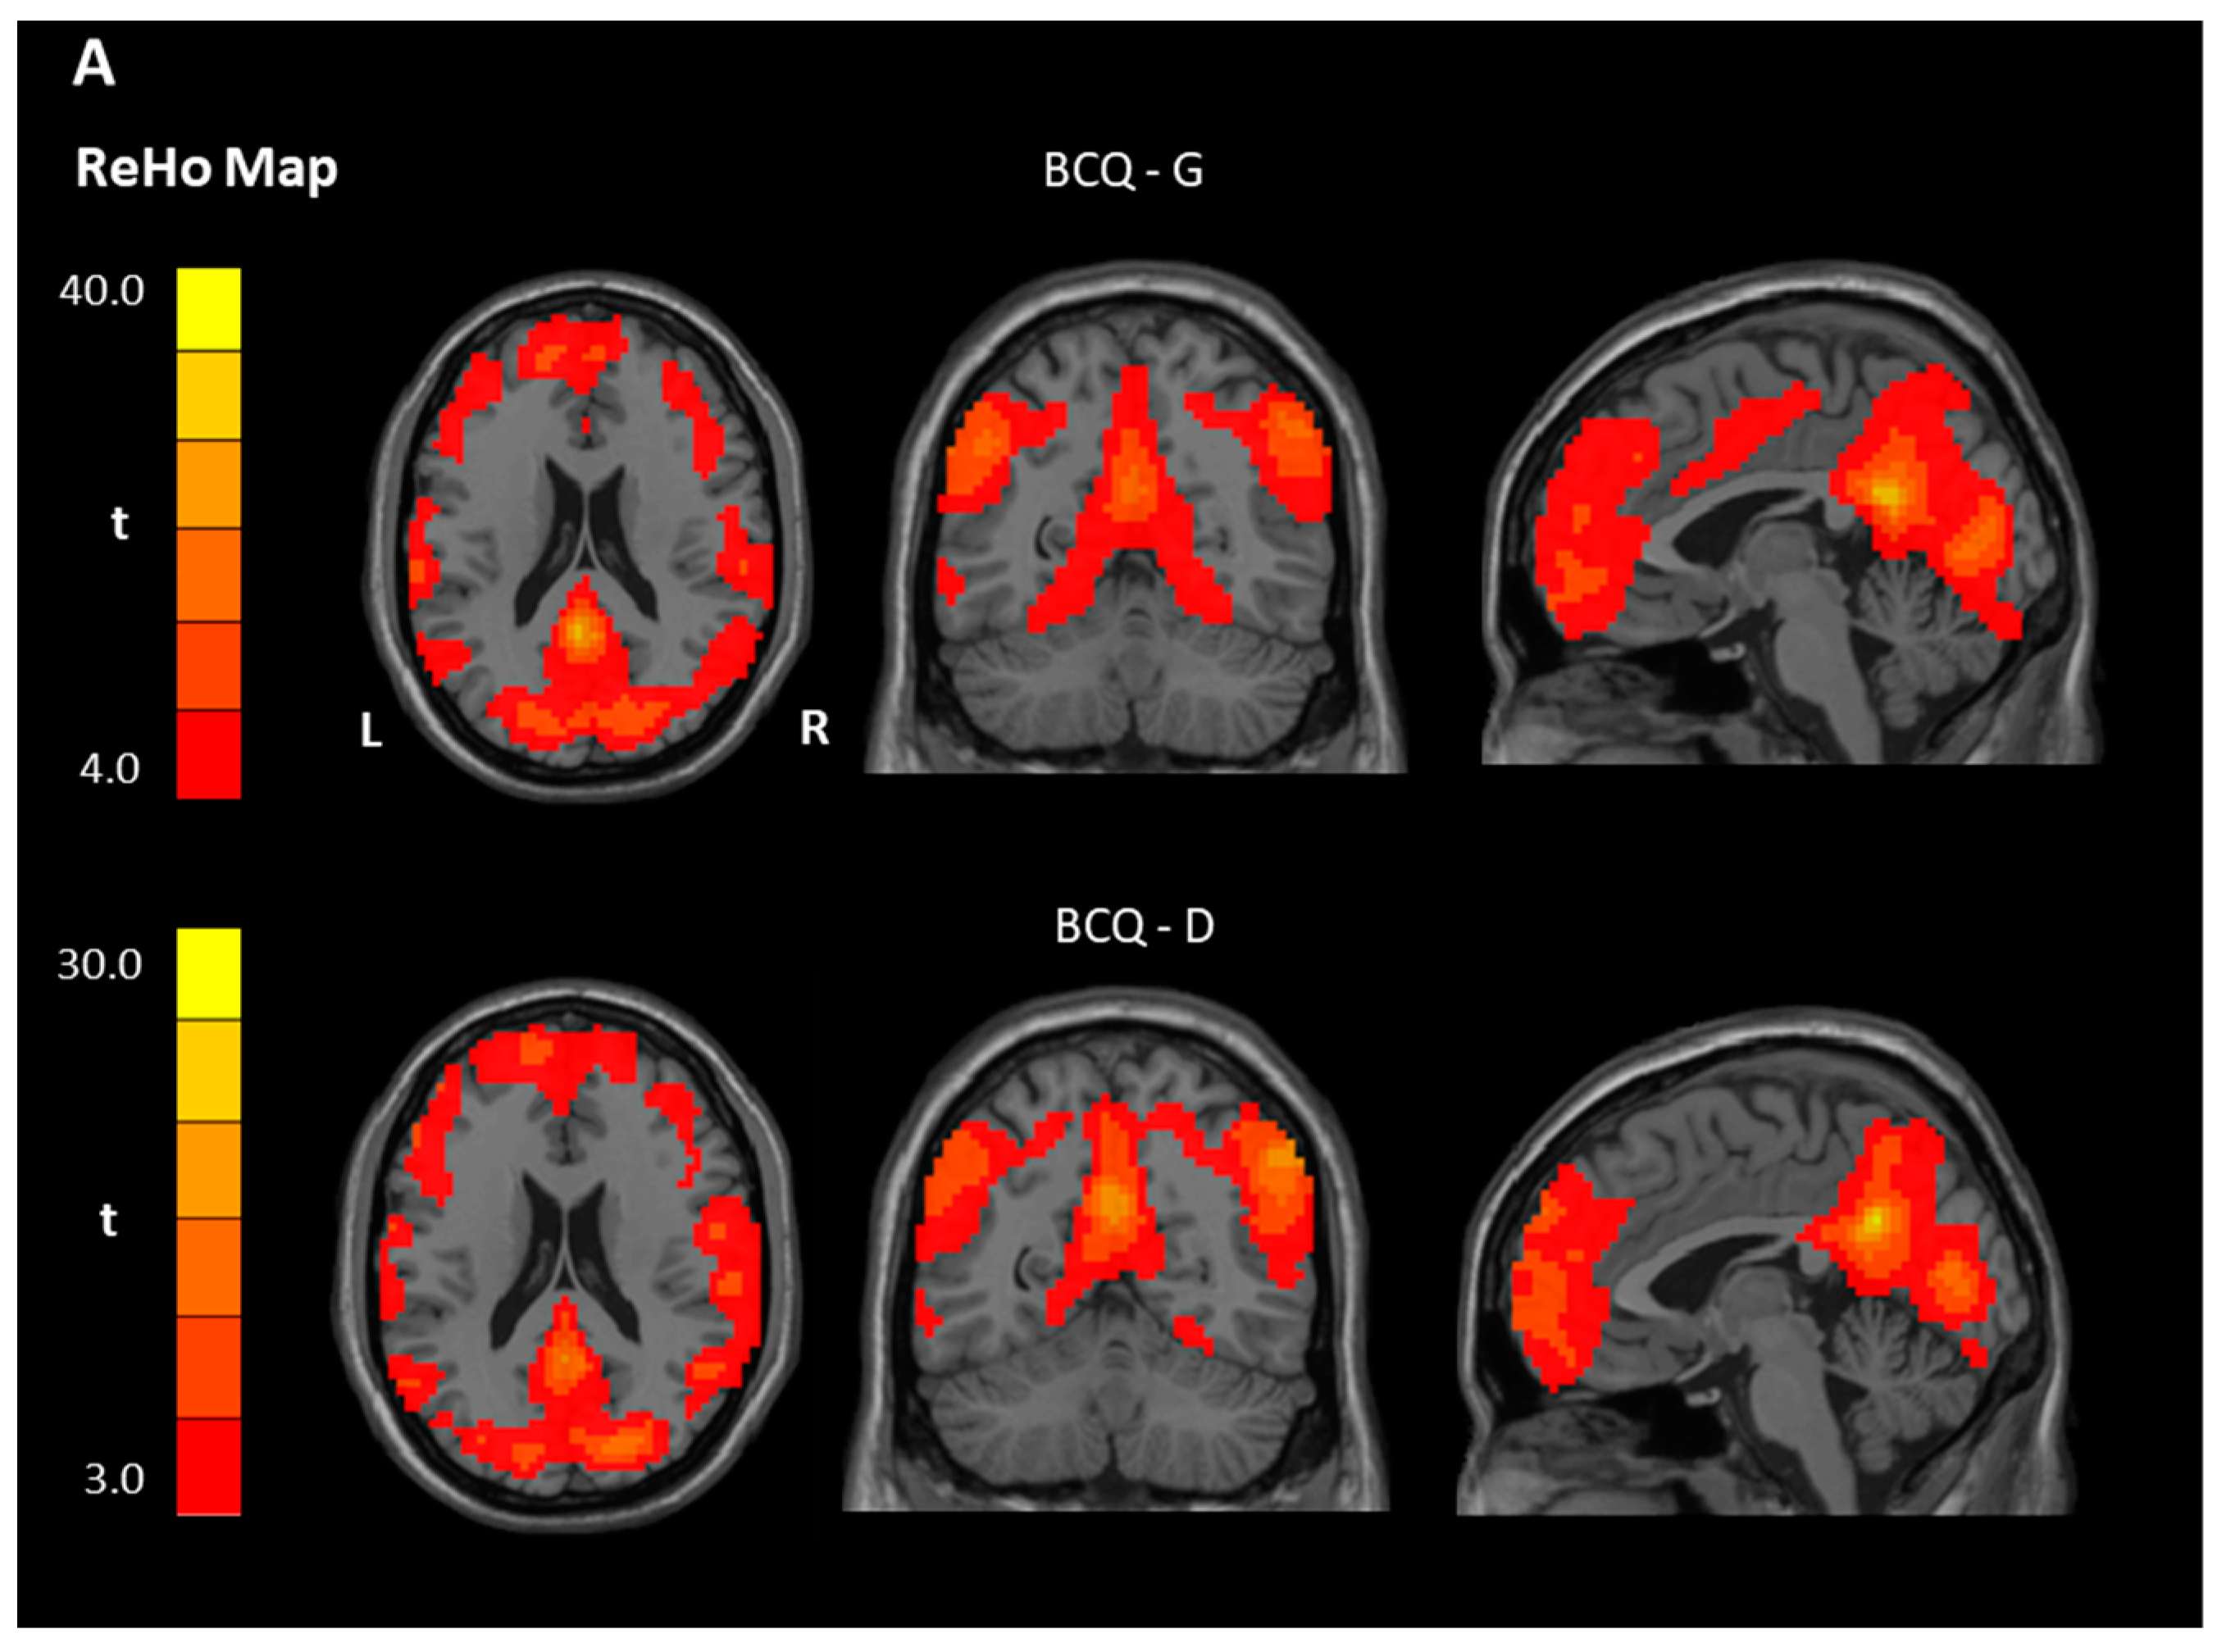

3.3. ReHo and ALFF Analyses

| Contrast | Region | BA | Size | t Score | Peak Coordinate | ||

|---|---|---|---|---|---|---|---|

| x | y | z | |||||

| ReHo | |||||||

| Within-group ** | |||||||

| BCQ-Gentleness | |||||||

| Gentleness > 0 | PCC, Left | 23 | 16,838 | 33.85 | −3 | −48 | 24 |

| Gentleness < 0 | NS | ||||||

| BCQ-Deficiency | |||||||

| Deficiency > 0 | PCC, Left | 23 | 8516 | 30.36 | −3 | −54 | 30 |

| OFC, Right | 11 | 4593 | 21.54 | 42 | 52 | −12 | |

| Deficiency < 0 | NS | ||||||